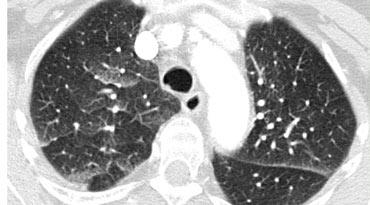

Ca lâm sàng minh họa: Phù phổi do tim

Hình ảnh: Chụp CT được thực hiện để loại trừ thuyên tắc phổi phát hiện sự kết hợp giữa dày vách đều, nhẵn và mờ kính mờ phân bố theo trọng lực.

Chẩn đoán là phù phổi do tim.

Đặc điểm chính của phù phổi do tim:

- Thường biểu hiện với dày vách liên tiểu thùy kết hợp mờ kính mờ.

- Phân bố quanh rốn phổi và theo trọng lực là đặc trưng của phù phổi thủy tĩnh.

- Các dấu hiệu bổ sung có thể bao gồm:

- Dày mô kẽ quanh phế quản-mạch máu (“viền quanh phế quản”)

- Dày rãnh liên thùy

- Tim to

- Tràn dịch màng phổi

- Mặc dù HRCT không được sử dụng thường quy để chẩn đoán (các dấu hiệu lâm sàng và X-quang thường đủ để kết luận), phù phổi thủy tĩnh không nghi ngờ trước đôi khi có thể được phát hiện tình cờ.